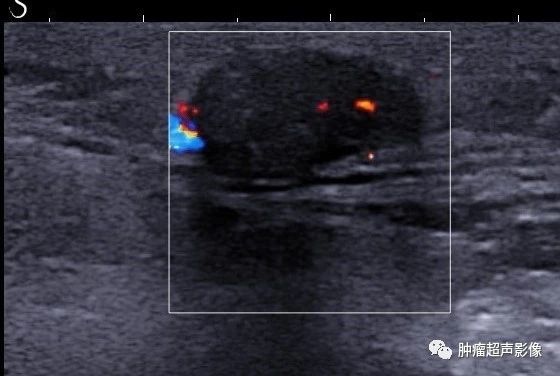

毛母质瘤又称钙化性上皮瘤,是一类源于人体毛发母细胞的良性肿瘤,青少年多见(可见于任何年龄),考虑与青少年毛发细胞及附件发育代谢旺盛有关。...